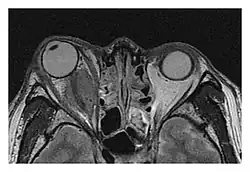

The extent of inflammation that can occur in IgG4-ROD is well demonstrated on magnetic resonance imaging (MRI).

Infraorbital nerve enlargement (IONE) is considered to be a particularly suspicious sign of IgG4-ROD, but seems to occur only when inflammation is in direct contact with the infraorbital canal.[10] IONE is defined as the infraorbital nerve diameter being greater than the optic nerve diameter in the coronal plane.